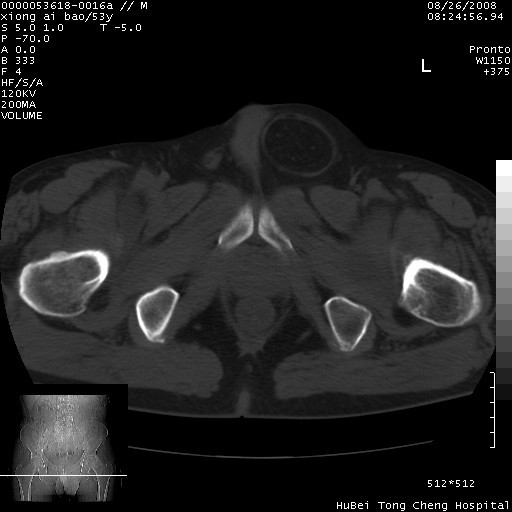

标题: CT15583:M,53Y。请老师指教分析骨盆及其他病变。 [打印本页]

标题: CT15583:M,53Y。请老师指教分析骨盆及其他病变。

双侧股骨头无菌坏死,左侧腹股沟斜疝。

非常典型病例,双侧股骨头坏死伴双髋关节周围软组织肿胀,左腹股沟疝。

双侧股骨头坏死伴双髋关节周围软组织肿胀,左腹股沟疝。

考虑双侧髋关节结核,左侧腹股沟疝